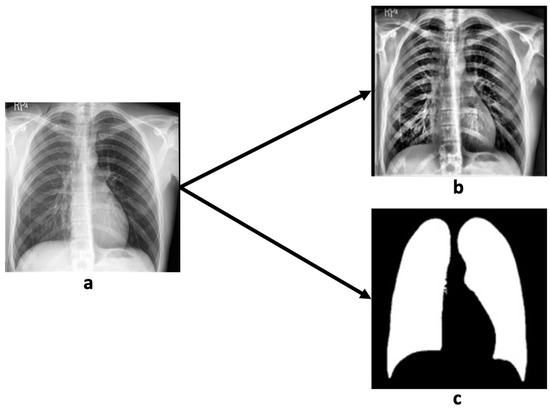

In this study, we use the Chest X-ray Anonymized Dataset in Dunedin—Pneumothorax (CANDID-PTX) benchmark dataset, which represents 19,237 chest radiographs (53.4% male subjects) [15]. The age range is 16–101 years (mean = 60.1 and STDEV = 20.1). In the dataset, 3196 chest radiographs are pneumothorax cases, while the remaining images are normal cases. The data were acquired from three imaging devices manufactured by Philips, GE Healthcare, and Kodak. Images were annotated using the MD.ai platform with free-form line marking. The image size was 1024 × 1024 pixels in DICOM format, and the segmentation ground truth is provided in RLE (run-length encoding) format. Figure 1 demonstrates a sample of the CANDID-PTX dataset, including both the original chest X-ray radiograph and the corresponding pneumothorax segmentation ground truth (converted from RLE format to a binary image). The 300 penumothorax cases we use in this dataset is randomly divided into five batches for a 5-fold cross-validation study.

Figure 1.

A sample from the CANDID-PTX dataset. Left is the original chest X-ray and right is the corresponding pneumothorax manual segmentation.

In this study, we apply contrast-limited adaptive histogram equalization (CLAHE) [27] to enhance the local contrast of chest X-ray images for improved pneumothorax detection, as illustrated in Figure 5. The process begins with the normalization of pixel intensities to the range [0, 1], ensuring consistent scaling across all images. CLAHE is then applied to enhance contrast within localized regions, thereby highlighting subtle features that are diagnostically significant. To prevent over-amplification of noise, the ClipLimit parameter is used to control the extent of enhancement. The resulting images are saved and displayed alongside their normalized counterparts for comparative visualization. This approach is particularly advantageous in medical imaging, where the ability to detect small but clinically important details is critical. By enhancing local contrast without significantly altering global image brightness, CLAHE supports more accurate interpretation while preserving the original image structure.

Figure 5.

A sample of contrast and lung segmentation by MedSAM demonstrates original chest X-ray radiograph (a), contrast-enhanced chest X-ray radiograph (b), and lung segmentation result (c).

3.4.2. Lung Segmentation by MedSAM

We employed MedSAM to perform automatic segmentation of lung regions in chest X-ray images. The process began by uploading the images to the MedSAM platform, where the lung fields were manually designated as regions of interest. MedSAM then utilized advanced deep learning algorithms in conjunction with image-processing techniques to automatically segment the lungs, effectively isolating them from adjacent anatomical structures such as the ribs and heart. To improve segmentation accuracy, users were able to refine the output by adjusting parameters or manually correcting boundary discrepancies. This semi-automated approach enabled precise delineation of lung regions, which is essential for identifying subtle abnormalities such as infections, tumors, or other pulmonary conditions [28].

As shown in Figure 5, MedSAM provided accurate and well-defined lung segmentation, thereby enhancing the detection and evaluation of lung-related pathologies and supporting radiologists in making more reliable and efficient diagnostic decisions based on chest X-rays.